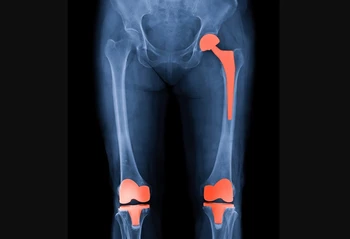

تصویربرداری پزشکی چیست؟ افراد به طور کلی نمی توانند به یک بیمار نگاه کنند و فوراً متوجه مشکل شوند. بیشتر مسائل پزشکی در داخل بدن رخ می دهد که از دید انسان خارج است، بنابراین تشخیص یک مشکل می تواند ...